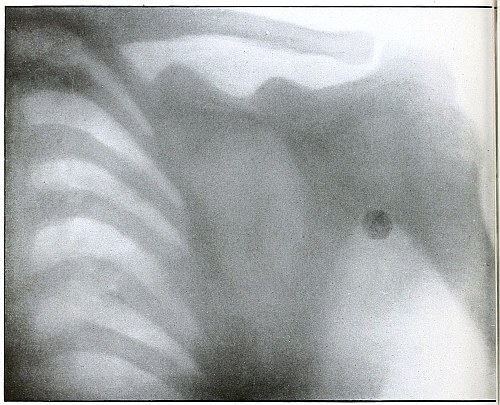

CHEST.

Plate 45.

_

[Pg 101]

Rifle—Plate 45.

Penetrating Gunshot Wound of the Chest,

with Lodgment of the Projectile Near Posterior Chest Wall.

Point of entrance, pectoral border and fourth rib.

Point of exit, none.

The distinct shadow of the angle of the ribs shows that the posterior chest wall was next to the photographic plate, and that the larger and less distinct outline of the anterior portions of the upper ribs was farther from the plate.

The nearly normal size of the shadow of the projectile shows it to be much nearer the posterior than the anterior chest wall. The blurred outline shows it to have moved with respiration. Such conditions locate its position within the thoracic cavity.

The emergency treatment is antiseptic dressing and rest.

The subsequent treatment depends upon pleural involvement or the extremely rare infection of the lung.

These cases are nearly all aseptic, and if the great vessels and nerves of the chest escape injury results are generally favorable. [Pg 102]